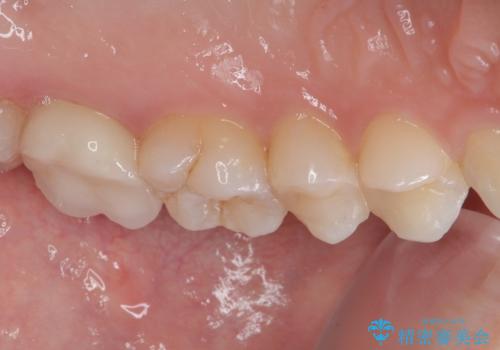

歯と歯茎の間に圧排糸と言われる糸を入れてシリコーン印象材にて型どりをしました。